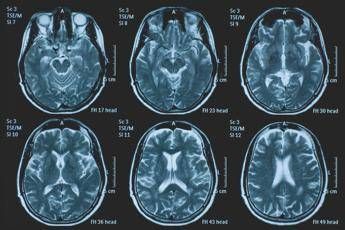

(Adnkronos) – La Commissione europea (Ce) ha autorizzato la commercializzazione condizionata di tovorafenib come monoterapia per il trattamento dei pazienti di età pari o superiore a 6 mesi con glioma pediatrico di basso grado che presentano una fusione o un riarrangiamento del gene Braf o una mutazione Braf-V600, in progressione di malattia dopo una o più terapie sistemiche precedenti. Lo annuncia Ipsen, in una nota, precisando che si tratta della “prima terapia mirata” per questa patologia e che la decisione della Ce si riferisce ai 27 Stati membri della Ue, oltre a Islanda, Liechtenstein e Norvegia. Ogni anno in Ue vengono diagnosticati più di 800 nuovi casi di glioma pediatrico di basso grado (pLgg) con alterazione di Braf. Questo tumore cerebrale, nonostante sia classificato di basso grado (a lenta progressione), comporta un carico significativo e permanente che accompagna la persona per tutta la vita, causando spesso importanti compromissioni fisiche e neurologiche, tra cui perdita della vista, difficoltà di linguaggio e disfunzioni motorie, che possono incidere in modo significativo sull’istruzione, l’autonomia e la qualità di vita a lungo termine del bambino. Finora, molti bambini con pLgg hanno dovuto sottoporsi a interventi chirurgici invasivi, a più cicli di chemioterapia e a radioterapia, con conseguenti complicazioni della salute. “Per i piccoli che ricevono la diagnosi di glioma di basso grado, il percorso è spesso lungo e difficile, con opzioni terapeutiche limitate – afferma Sandra Silvestri, Executive Vice President and Chief Medical Officer, Ipsen – Questa approvazione rappresenta un passo avanti significativo per questi bambini e per le loro famiglie, rafforzando al contempo il nostro impegno a rispondere a elevati bisogni clinici non soddisfatti. Ora il nostro obiettivo è garantire che i bambini eleggibili in tutta Europa possano accedere a questa terapia il più rapidamente possibile”. L’approvazione della Ce si basa sui dati dello studio di fase 2 Firefly-1 che ha valutato tovorafenib in 137 bambini e giovani adulti con pLgg recidivato o refrattario con alterazioni di Braf che avevano ricevuto almeno una precedente terapia sistemica. Nel dettaglio, lo studio ha dimostrato una risposta tumorale clinicamente significativa con un tasso di risposta globale del 71% secondo i criteri Rano-Hgg (ResponseAssessment in Neuro-Oncology criteria for High-Grade Gliomas) e del 53% secondo i criteri Raono-Lgg (Response Assessment in Paediatric Neuro-Oncology for Low-Grade Glioma), con un tasso di beneficio clinico del 77% secondo i criteri Rano-Hgg e del 58% secondo i criteri Rapno-Lgg. Le risposte – riferisce la nota – sono state rapide e durature: sulla base dei criteri Rapno-Lgg, tra coloro che hanno risposto, il tempo mediano alla risposta è stato di 5,4 mesi con una durata mediana della risposta di 18 mesi. Sul profilo di sicurezza, tovorafenib è stato generalmente ben tollerato, con eventi avversi legati al trattamento (Traes) prevalentemente di grado 1 o 2 e un tasso di interruzione basso (9,5% dei pazienti ha interrotto il trattamento a causa di eventi ritenuti dallo sperimentatore correlati a tovorafenib). I Traes più comuni comprendevano variazione del colore dei capelli, creatinfosfochinasi ematica alta, fatigue, anemia, vomito, ipofosfatemia, cefalea, eruzione cutanea maculopapulare, febbre, ritardo della crescita, secchezza cutanea. Il regime posologico semplice, con la somministrazione orale una volta alla settimana, con o senza cibo, in formulazione liquida o in compresse, ha ridotto al minimo i disagi nella routine quotidiana. Le famiglie con piccoli colpiti dal glioma di basso grado “spesso devono affrontare anni di incertezza, difficili decisioni terapeutiche e il timore delle conseguenze a lungo termine”, evidenzia François Doz, professore di Pediatria alla Paris Descartes University, vicedirettore di Clinical Research, Innovation and Teaching al Siredo Oncology Centre of the Curie Institute (Assistenza, innovazione e ricerca nel campo dei tumori dell'infanzia, dell'adolescenza e dei giovani adulti) e direttore didattico dell’Hospital Ensemble of the Institut Curie. Il regolamento dell'Ue sulla valutazione delle tecnologie sanitarie (Health Technology Assessment – Hta -Regulation), la cui attuazione è iniziata progressivamente a partire da gennaio 2025 – conclude la nota – ha introdotto un nuovo processo di valutazione clinica congiunta (Joint Clinical Assessment – Jca) volta a semplificare e armonizzare la revisione comparativa delle evidenze cliniche negli Stati membri dell'UE. Tovorafenib è il primo farmaco a essere sottoposto a una valutazione Jca.

Tumori, glioma pediatrico di basso grado: via libera in Europa a prima terapia mirata